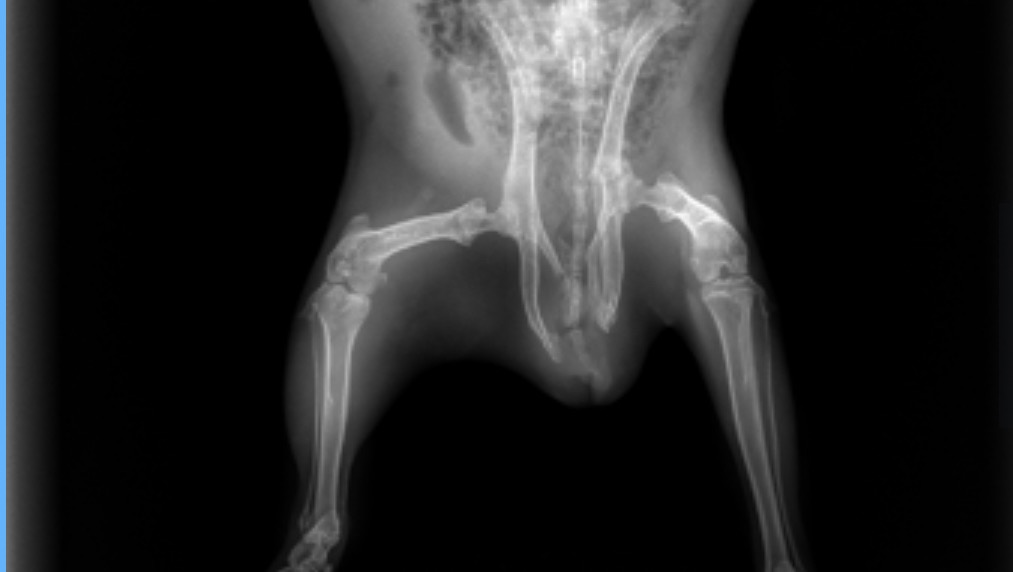

Thora’s story is heartbreaking. She was brought to me after someone admitted that they had intentionally dumped her outside. I called animal control and when the officer picked her up, she was underweight, struggling to walk, and clearly in pain. I brought her to an emergency vet right away, and x-rays showed that her pelvis is fractured in multiple places.

Even with these serious injuries, Thora has shown a strong will to live. She’s eating well, has a big appetite, and can use the bathroom normally. She will need cage rest for several weeks, followed by physical therapy and supportive treatments like laser therapy and acupuncture.

So far, her emergency care has already cost over $1,000. This includes sedation, radiographs, IV fluids, pain medications, and the emergency exam. She will continue to need ongoing veterinary visits and pain control.